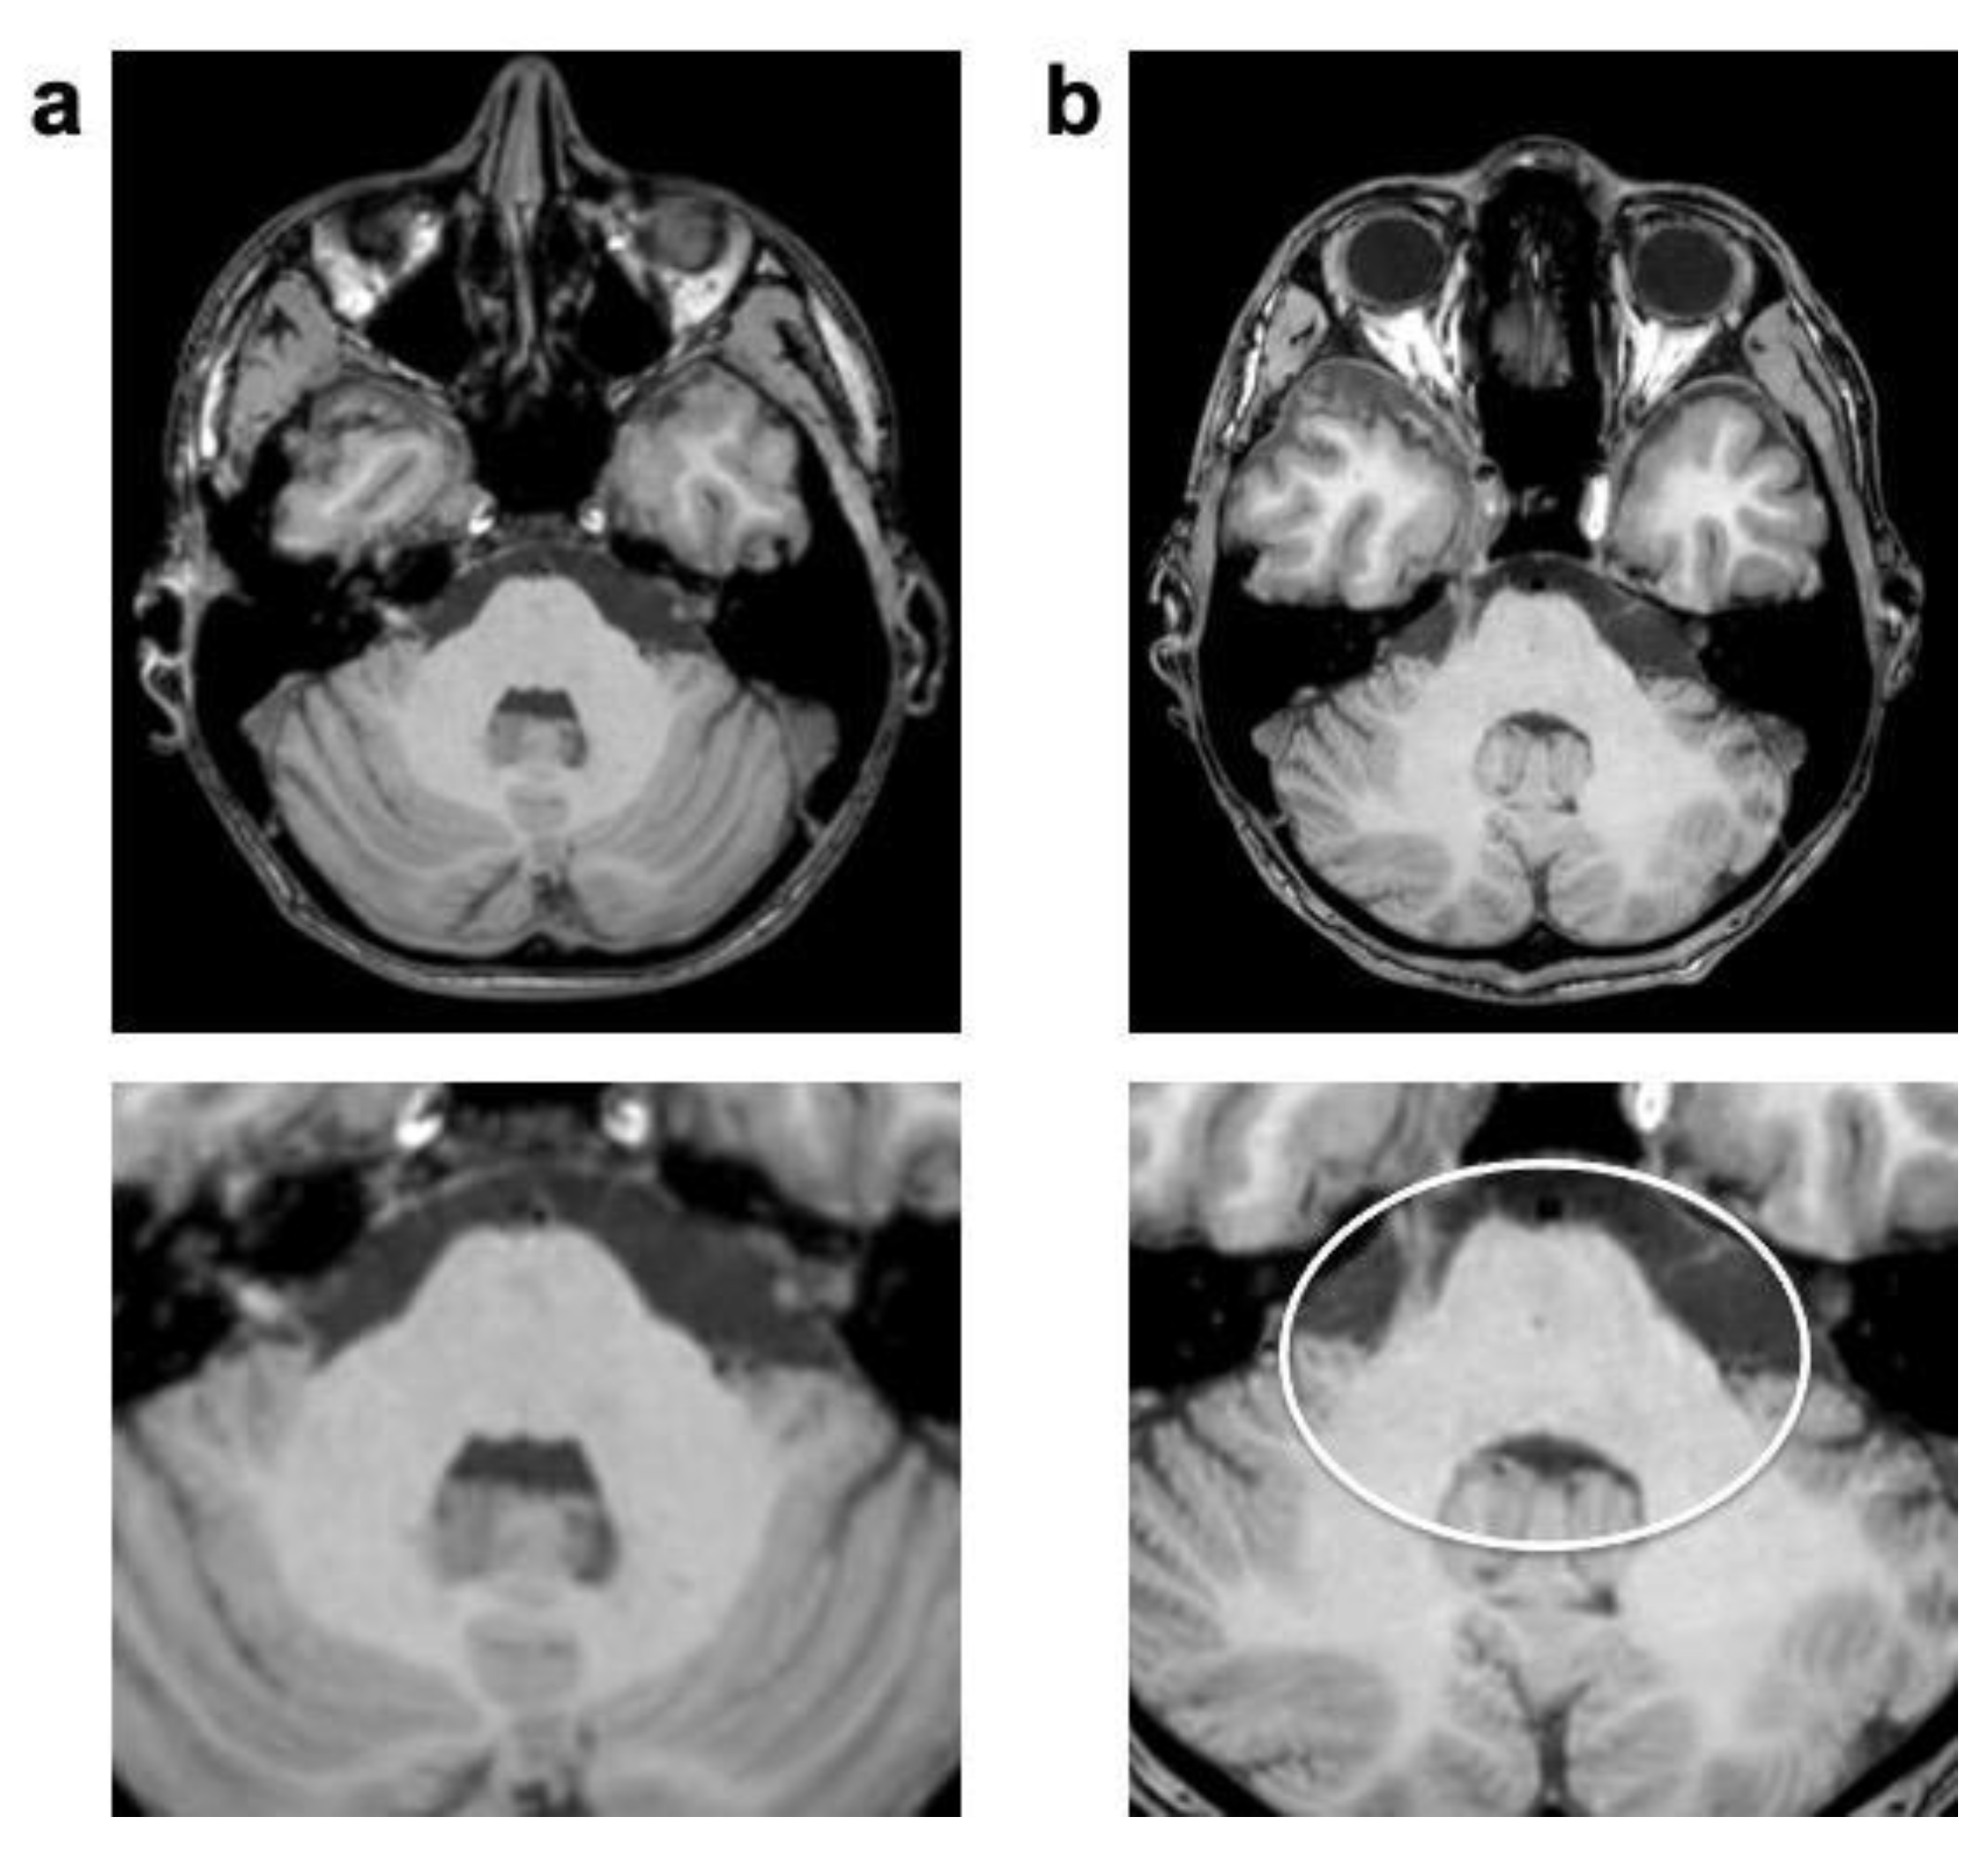

The “Wax-layer” artifact presented as patchy inhomogeneous blurring of brain structure mainly in post-contrast CS 3D T1 TFE (Figure 5).

Figure 5.

Enhanced 3D T1 TFE images of a 12-year-old male patient with non-germinomatous germ cell tumor (not shown). Wax-layer artifact presenting as patchy to blurred signal inhomogeneity in the pons and cerebellum in CS (b); not present in previous SENSE study (a).